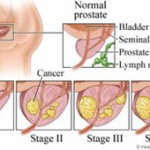

Τα στάδια του αδενοκαρκινώματος του προστάτη

- Χαμηλής επικινδυνότητας (Low Risk): Ασθενείς με PSA λιγότερο από 10 ng/ml (PSA<10), έχουν Gleason Score μικρότερο ή ίσο του 6 (Gleason <= 6) και είναι σταδίου T1 ή Τ2a.

- Μέσης επικινδυνότητας (Medium Risk): Ασθενείς με PSA από 10 – 20 ng/ml (PSA 10 – 20), έχουνGleason Score ίσο με 7 (Gleason = 7) και είναι σταδίου Τ2b.

Οι ασθενείς μέσης επικινδυνότητας, επειδή βρίσκονται σε μέτριας βαρύτητας στάδιο, μπορούν να εφαρμόσουν συνδυασμό τουλάχιστον δύο μεθόδων από τις τρεις ακόλουθες: τη χειρουργική, την ακτινοθεραπεία και την ορμονοθεραπεία (με σχεδόν όλες τις υποκατηγορίες τους). Φυσικά θα ενημερωθούν από τον ουρολόγο τους για τις παρενέργειες και επιπλοκές κάθε συνδυασμού. Η θεραπεία περιλαμβάνει κυρίως τον προστάτη αδένα, αλλά προστατευτικά καλύπτει και τους περιβάλλοντες ιστούς μαζί με τους ανάλογους λεμφαδένες επειδή υπάρχει αυξημένη πιθανότητα διηθήσεως της κάψας του αδένος, των σπερματοδόχων κύστεων και ίσως ύπαρξη μικρομεταστάσεων στους επιχώριους λεμφαδένες.

Υψηλής επικινδυνότητας (High Risk): Ασθενείς με PSA μεγαλύτερο των 20 ng/ml (PSA > 20), έχουνGleason Score ίσο ή μεγαλύτερο του 8 (Gleason >= 8) και είναι σταδίου T2c, Τ3 ή Τ4.

Οι ασθενείς υψηλής επικινδυνότητας, επειδή βρίσκονται σε σχετικά προχωρημένο στάδιο, πρέπει να εφαρμόσουν συνδυασμό ορμονοθεραπείας και εξωτερικής ακτινοθεραπείας και ίσως επικουρικά κάποια χειρουργική μέθοδο. Σε αυτούς, υπάρχει ανάγκη γενικότερης θεραπείας του οργανισμού και όχι μόνο τοπικής στον προστάτη αδένα, γιατί οι πιθανότητες υπάρξεως εξωπροστατικής διασποράς του αδενοκαρκινώματος είναι πολύ μεγάλες (σχεδόν βέβαιες).